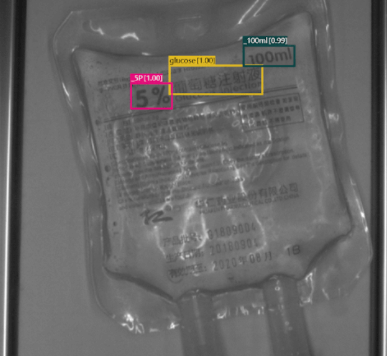

With SolVision‘s segmentation tool, various labels can be identified from sample images to train a visual inspection system capable of classifying information on IV bags based on their distinctive features. SolVision’s advanced AI-based technology is also unaffected by transparent objects, label complexity, or appearance.

Dextrose Solution